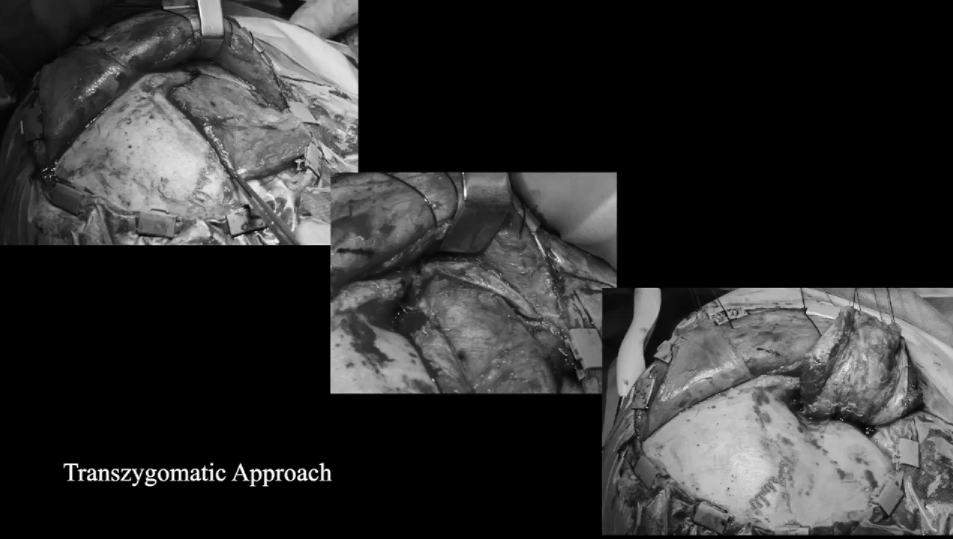

▼使用顴弓入路手術(shù),利用筷子技術(shù)神經(jīng)內(nèi)鏡+顯微鏡次全切除腫瘤,從海綿竇剝離硬腦膜,切除了浸潤的硬腦膜和向顳部延伸的硬膜上腦膜瘤。

使用顴弓入路手術(shù),利用筷子技術(shù)神經(jīng)內(nèi)鏡+顯微鏡次全切除腫瘤,從海綿竇剝離硬腦膜,切除了浸潤的硬腦膜和向顳部延伸的硬膜上腦膜瘤。